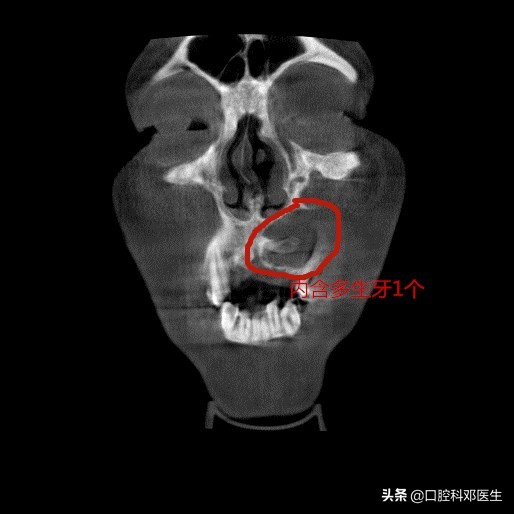

冠状位片

接诊的邓医生介绍:这位患者脸肿大是由于左侧上颌骨内一个埋伏多生的牙齿所引起的,由于牙齿无法正常萌出,经过时间的积累,从而诱发囊肿,囊肿一般都不痛不痒,越长越大,像鼓气球一样,逐渐破坏了周围的骨头,如破坏上颌骨前壁,就会突破至软组织,引起脸部肿大;如破坏牙槽骨,则会导致牙齿松动移位,引起牙根吸收疼痛等症状。